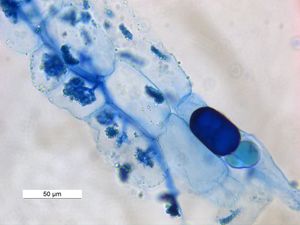

3. 2. 생물학적 염색

트리판 블루는 현미경을 이용한 세포 계수와 조직 생존력 평가를 위해 실험용 쥐에서 일반적으로 사용된다.[16] 이 방법으로는 괴사 세포와 세포 사멸 세포를 구별할 수 없다.진균 균사 및 스트라메노필을 관찰하는 데 사용할 수 있다.[17]